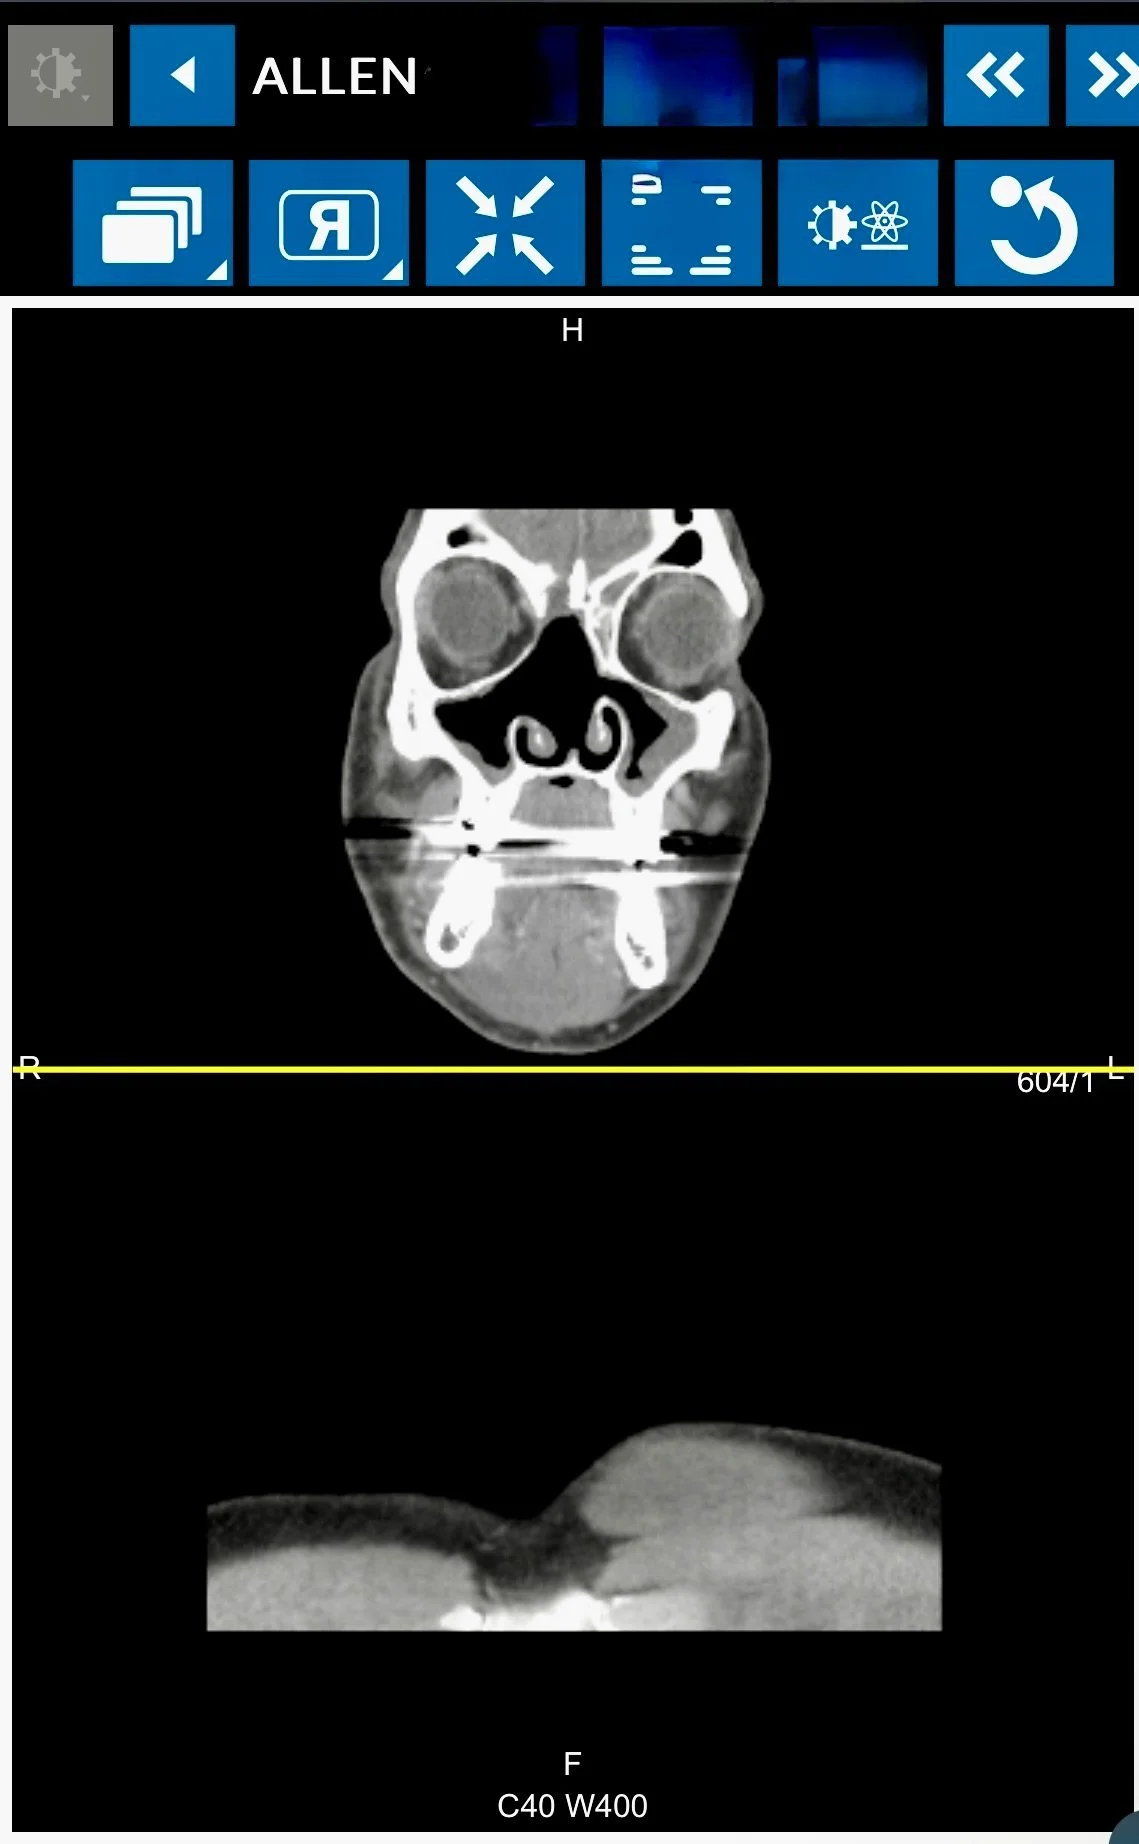

Soon afterward, a follow-up MRI revealed abnormal lumps in two lymph nodes in my neck, one of which tested positive for metastatic cancer. This marked my third battle with the disease since 2016 and became a significant breaking point in my life.